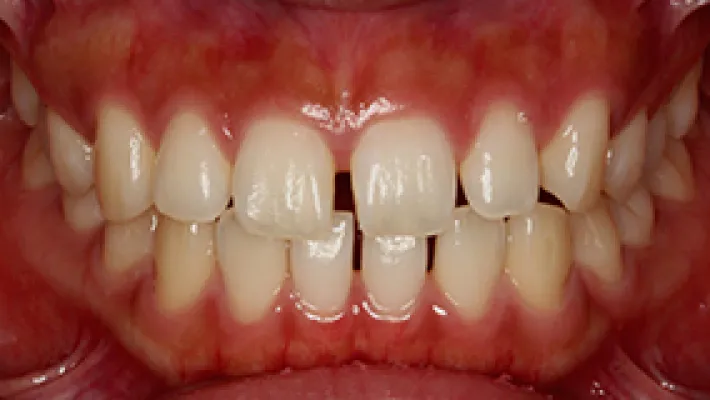

施術前

施術後

マウスピース矯正の部分矯正で上下前歯のすきっ歯を改善した症例です。

状態にもよりますが、すきっ歯はマウスピース矯正の得意とするケースの一つです。

効率的な治療計画で最小限の期間と負担で矯正を行いました。

矯正治療の期間・方法

矯正治療の期間や方法は歯並びや顎骨などの状態によって大きく異なります。

矯正治療は歯や歯周組織などに必ずダメージがあります。

矯正治療のダメージを最小限にするために健康的で現実的な治療計画を提案します。

治療費

420,000

治療期間

4.5ヶ月